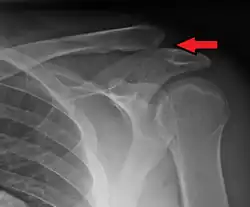

| An Xray showing a separated shoulder. Notice the separation between the end of the collarbone and the scapula. | |

A separated shoulder, also known as acromioclavicular joint injury, is a common injury to the acromioclavicular joint.[2] The AC joint is located at the outer end of the clavicle where it attaches to the acromion of the scapula.[2] Symptoms include non-radiating pain which may make it difficult to move the shoulder. The presence of swelling or bruising and a deformity in the shoulder is also common depending on how severe the dislocation is.[2][1]

X-ray indicates a separated shoulder when the acromioclavicular joint space is widened (it is normally 5 to 8 mm).[9]